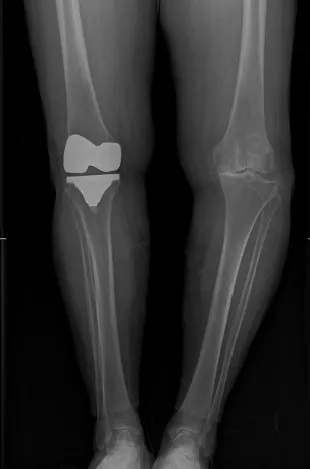

① X线:为膝骨关节炎明确临床诊断的“金标准”,是首选的影像学检查。X线片上的三大典型表现为受累关节非对称性关节间隙变窄、软骨下骨硬化和(或)囊性变、关节边缘骨赘形成。部分患者可有不同程度的关节肿胀,关节内可见游离体,甚至关节变形。

④ 单髁置换术:对于只是膝关节内侧髁磨损,外侧髁依然完好的患者,单髁置换手术将是更好的选择。这种人工关节保留了外侧髁、髌骨、交叉韧带等结构,与传统的全膝关节置换术相比,提供更多的生理功能、更大的活动范围、以及更快的术后恢复。

⑤ 人工关节表面置换术:俗称“换膝”手术,是20世纪最成熟的手术方式之一,已成为严重膝骨关节患者的救星。通过对膝关节的表面进行精确的截骨矫形,安装上寿命20年以上的人工关节假体,让历经磨难的膝关节焕然一新,返老还童。由于手术风险低,效果好,对于50岁以上患有膝关节骨关节炎,生活质量受到严重影响的患者非常适用。